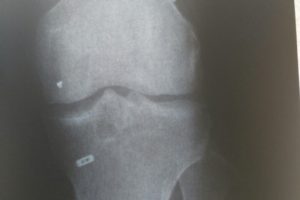

При рентгенографическом исследовании выявляются только хотя бы частично кальцифицированные свободные тела. Свободные тела, полностью состоящие из хряща, встречаются наиболее часто и совершенно неразличимы на рентгенограммах.

Во всех случаях необходимо выполнить рентгенографию в двух проекциях. Для чёткой оценки межмыщелковой вырезки рекомендовано исследование в проекции Розенберга (переднезадняя проекция в положении сгибания в коленном суставе на 45°).

Другим вариантом для этих целей является туннельная проекция Фрика. В некоторых случаях необходимы дополнительные косые (30°, 45°) или функциональные проекции. Проекция с максимальным сгибанием в коленном суставе обеспечивает наиболее чёткую картину передней межмыщелковой области для подтверждения или исключения наличия свободных тел, оссификатов или краевых остеофитов.

- Рентгенограмму коленной области;

- Компьютерную томограмму.

Они наглядно демонстрируют дополнительное плотное образование, не связанное с какими-либо суставными структурами. Если это образование не выявляется во время рентгенограммы, выполняют снимок с контрастированием воздухом (пневмоартрография) или двойным контрастированием (контрастное вещество и воздух).